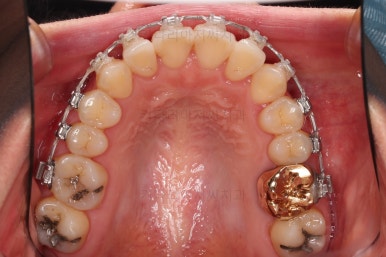

초진 시, 입안의 모습입니다.

좌측 송곳니가 덧니처럼 튀어나가 있고, 송곳니 옆의 작은 억므니가 안으로 쏙 들어가서 덧니 느낌이 더 강조되어 보이네요.

위아래 앞니가 긴밀하게 겹침이 없는 약간의 개방교합(오픈바이트, Openbite) 경향이 보입니다.

이번에 선택하신 장치는 자가결찰 세라믹 중에 엠파워 클리어라는 장치인데요.

흔히들 아시는 클리피씨도 같은 분류의 장치입니다.

철사가 들어가니 삐뚤한 치열이 더 강조되어 보이네요.